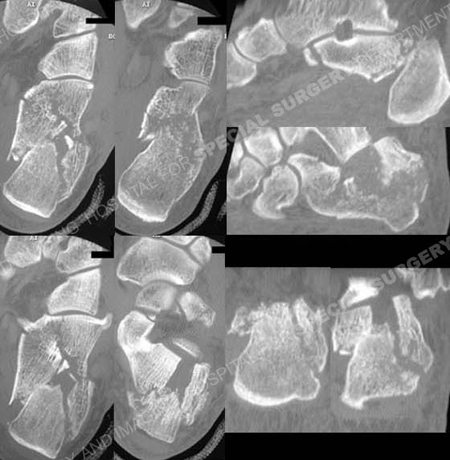

CT scan images further delineating the fracture pattern.